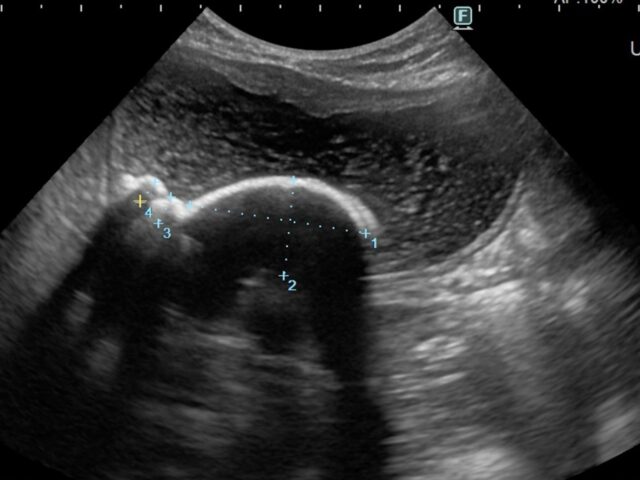

動物用CTを用いた検査が可能です。経験豊かな獣医師が患者様の状況に合わせて最善の検査・治療をご提案いたします。また、軟部組織外科など難度の高い手術症例にも対応しています。